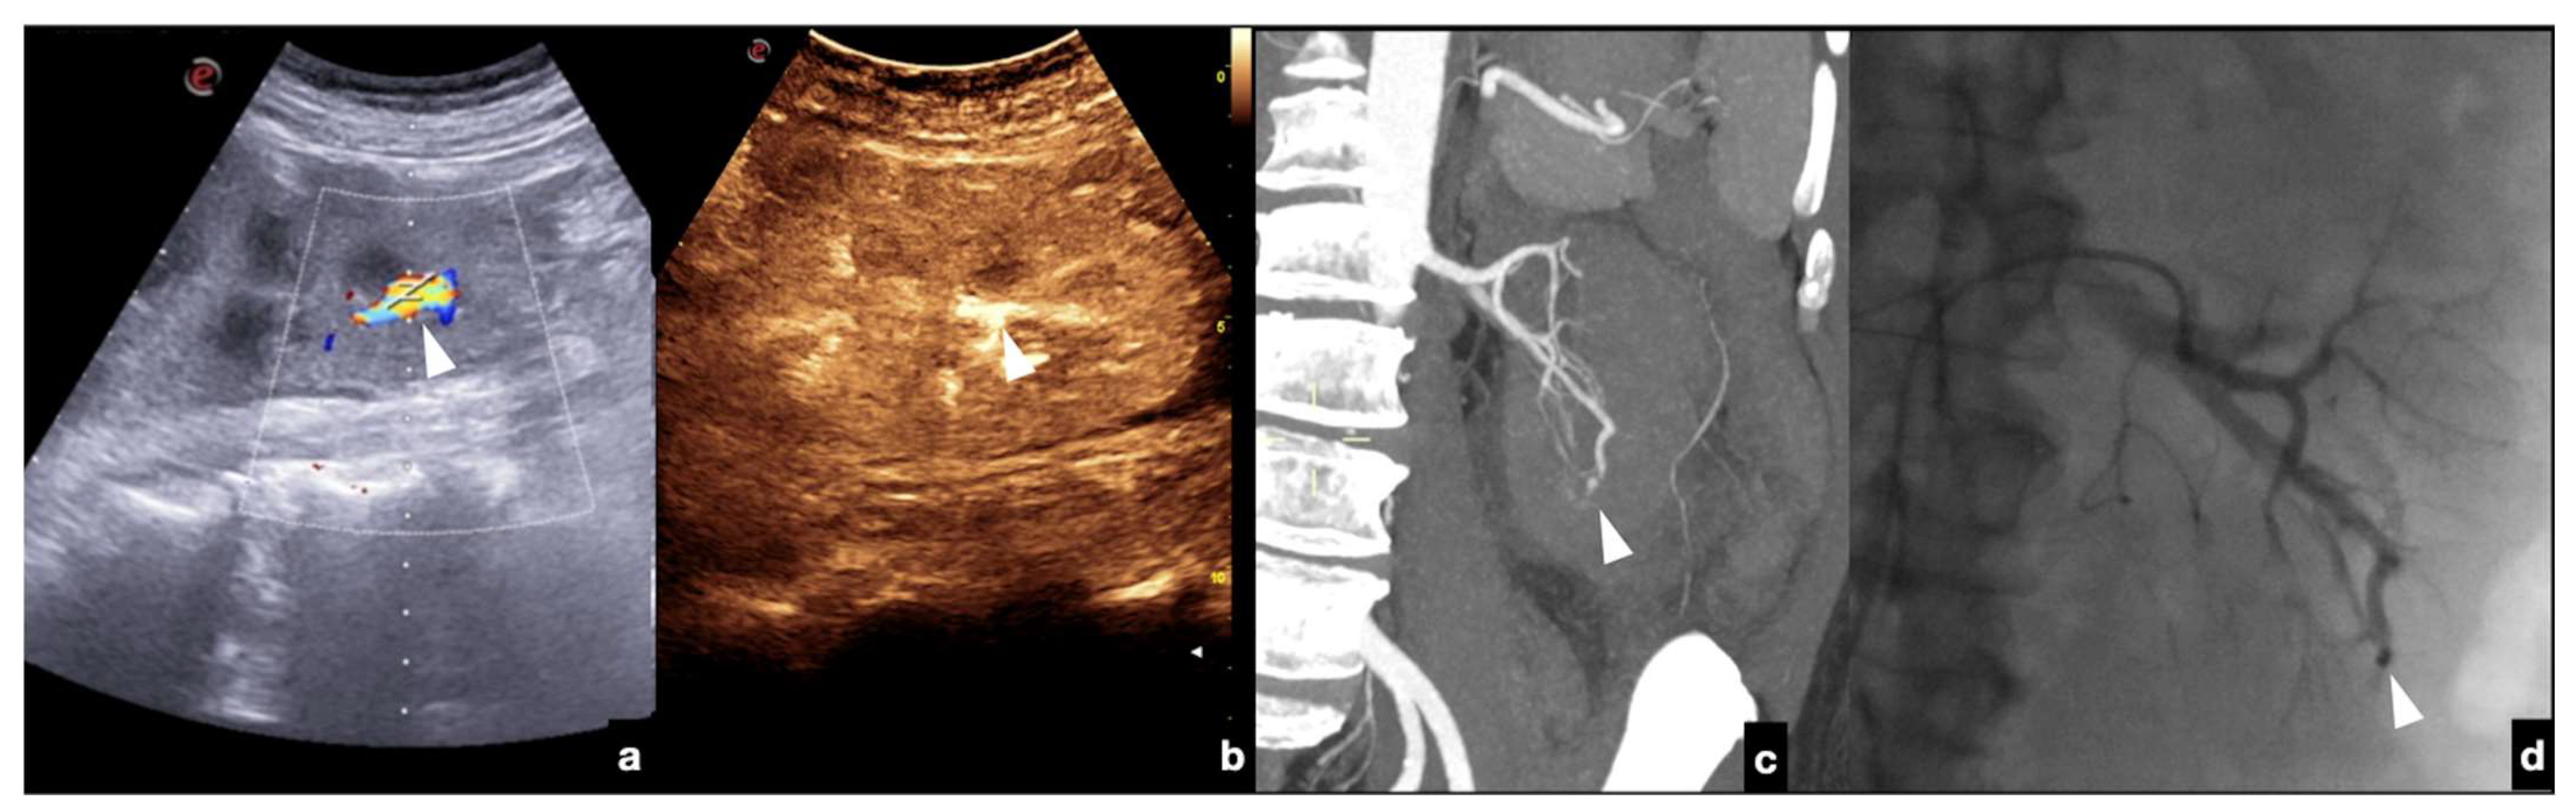

- Contained vascular injuries: